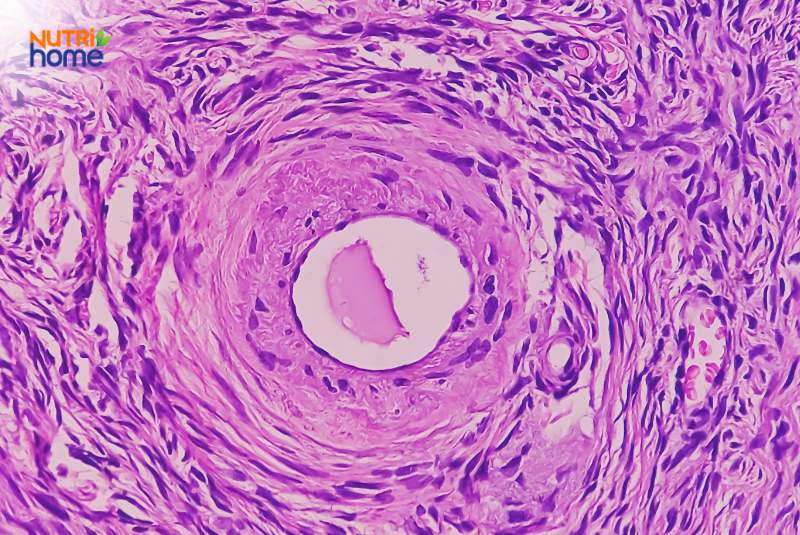

Minh họa hình ảnh u lành tính ở buồng trứng